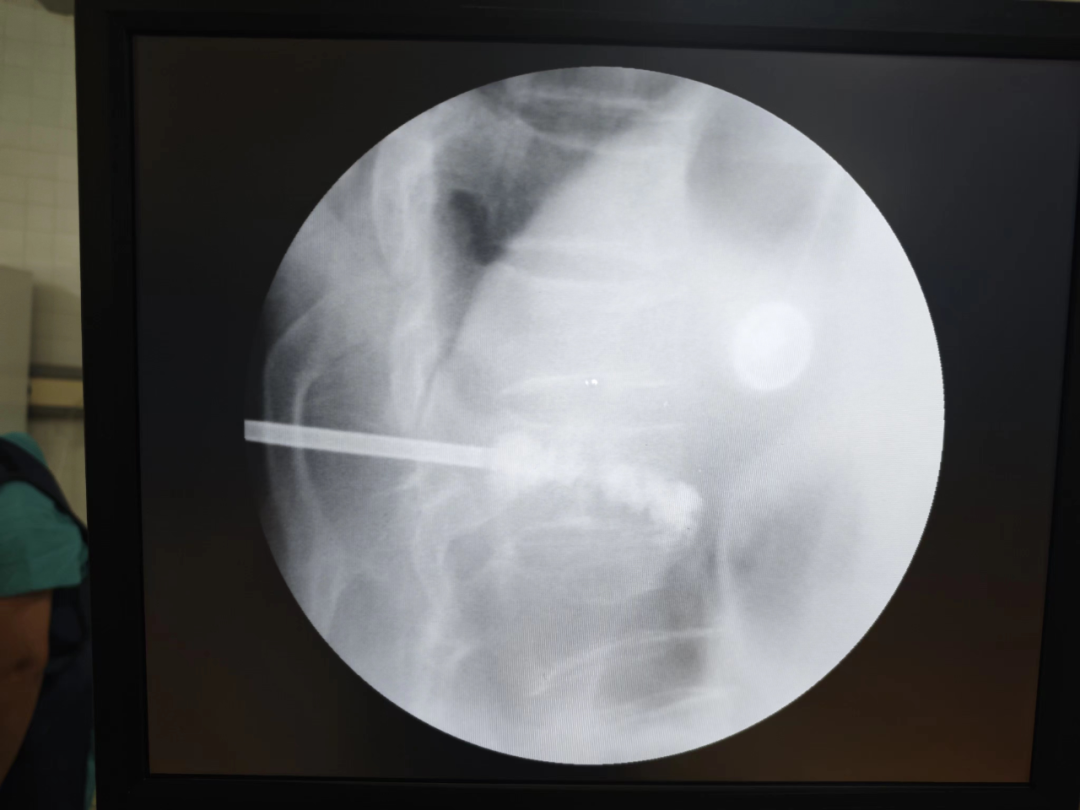

病例回顧 骨折部位 術(shù)中C臂協(xié)助定位 在C-臂監(jiān)視器透視下,分別定位胸12雙側(cè)椎弓根位置,標記穿刺點,僅以穿刺點為中心做3mm切開,在透視下注入骨水泥,再次透視見骨水泥位置良好。 骨水泥注入 術(shù)后影像學檢查 手術(shù)切口1cm左右 該手術(shù)經(jīng)皮透視下穿刺,手術(shù)切口小,創(chuàng)傷小,無需縫合,術(shù)后患者即感腰部疼痛明顯減輕,第二天可下床行走,已無腰痛不適,張大娘非常高興,自己再也不會受腰痛折磨整日與床為伴了。 我院脊柱骨科近年來,已成功開展多臺PVP手術(shù),為廣大老年患者減輕了病痛,減少了患者臥床時間,提高了生活質(zhì)量,是骨質(zhì)疏松性椎體骨折患者的福音。如果家里的老人突然出現(xiàn)了腰背疼痛,翻身下床困難,或者出現(xiàn)了腹部不適,排除腹部疾病(因為很多胸腰椎骨折患者在早期以腹痛腹脹為最主要癥狀),無論有沒有外傷史,建議帶老人及早就醫(yī),如果發(fā)現(xiàn)椎體損傷,積極治療,讓老人度過一個輕松愉快的晚年生活。 科普小講堂:經(jīng)皮椎體成形術(shù) 什么是骨質(zhì)疏松性椎體骨折? 骨質(zhì)疏松性椎體壓縮骨折,即在日常生活中患者并未遭受到明顯的外力而發(fā)生的骨折。這種骨折與創(chuàng)傷性的骨折不同,是由于自身骨質(zhì)疏松所導(dǎo)致的骨組織病變。骨質(zhì)疏松性骨折發(fā)生時,患者會感覺到背部明顯疼痛,翻身或起床等動作會讓疼痛更加明顯。 骨質(zhì)疏松性椎體壓縮骨折的危害有哪些? 一旦椎體發(fā)生骨質(zhì)疏松性椎體壓縮骨折,常常會導(dǎo)致患者出現(xiàn)腰背部持續(xù)性疼痛、季肋部放射痛、后凸畸形、呼吸功能受限及胃腸道癥狀等諸多癥狀,造成老年患者生活質(zhì)量下降。 什么是經(jīng)皮椎體成形術(shù)? (Percutaneousvertebroplasty,PVP)是一種新型的脊柱微創(chuàng)手術(shù),通過采用經(jīng)皮穿刺的方法,經(jīng)過椎弓根或是直接向椎體中注入骨水泥,使得椎體的強度和穩(wěn)定性得以提升,防止塌陷,從而達到緩解腰背疼痛,甚至部分恢復(fù)椎體高度的目的。 PVP手術(shù)優(yōu)點是什么? 1.恢復(fù)顯著:通常術(shù)后6個小時即能達到穩(wěn)定固定,患者可下床站立活動,大大縮短了患者臥床的時間。 2.疼痛減輕:術(shù)后患者會發(fā)現(xiàn)腰背部疼痛明顯減輕。 3.微創(chuàng):該治療方法僅需在皮膚上留2-3mm的穿刺針孔。 4.安全性:由于手術(shù)采用的是局部麻醉,因此即便是存在多種基礎(chǔ)病的患者也能夠耐受手術(shù),整個手術(shù)過程相對安全。 就診地址 酒泉市中醫(yī)醫(yī)院四樓脊柱骨科 咨詢電話 一樓門診部:0937-2669161 王醫(yī)生:13209409826 ??? 張醫(yī)生:18219971722